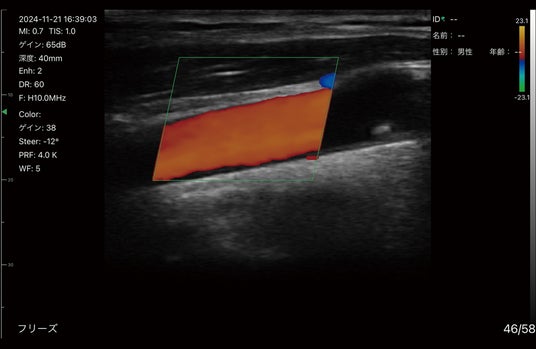

コンベックスとリニアプローブを一体化したデュアルプローブと、血流を視覚的に表示するドプラ機能の搭載により、1台で幅広い領域/部位へ使用可能。

▲カラードプラ使用イメージ(頸動脈)